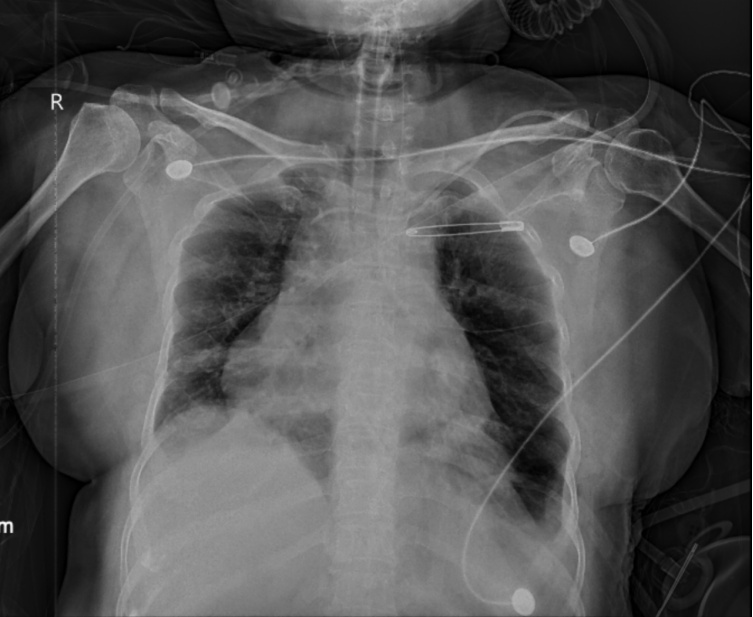

这时,ICU团队请胸外科李鹤成主任会诊。结合CT和胸片,李主任发现了被忽视的关键问题——陈阿姨的左侧膈肌严重松弛抬高,左肺被压缩得几乎无法正常工作。此前外院曾考虑“膈疝”,但经进一步评估,胸外科团队明确诊断为膈肌松弛——膈肌并没有破洞,而是整块肌肉失去了张力,无法正常收缩。

手术很成功——术后复查CT显示,左下肺明显复张,被压缩的肺终于重新“打开”了。

【术后胸片:左侧膈肌位置恢复,左下肺复张】